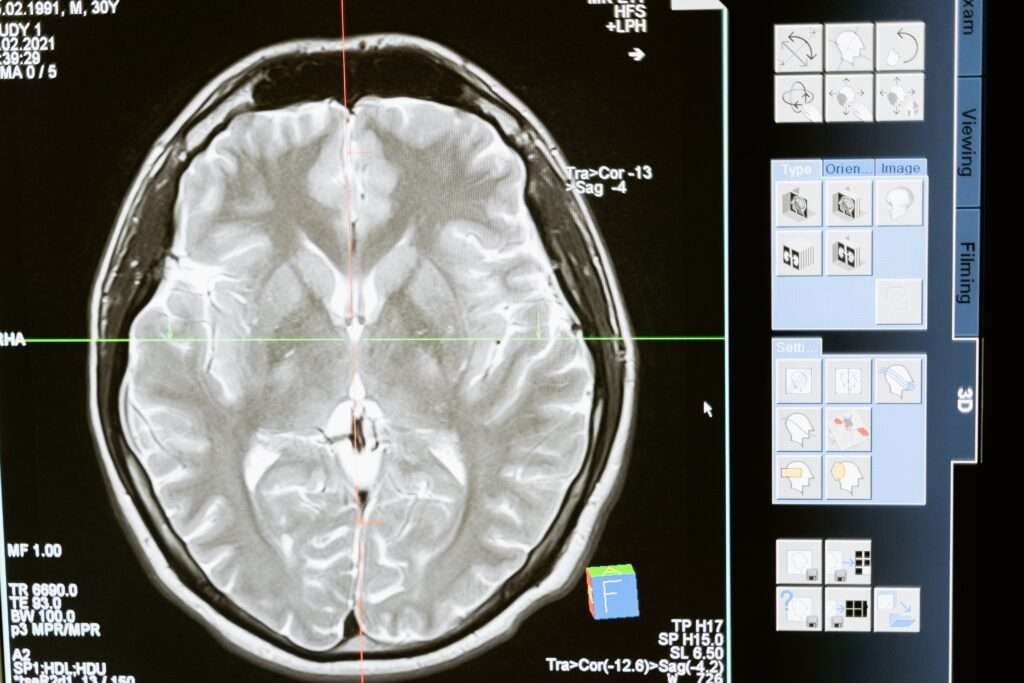

Magnetic Resonance Imaging (MRI) is a non-invasive diagnostic imaging technology that uses strong magnetic fields and radio waves to produce detailed images of the body’s internal organs and tissues. MRI technology is widely used in medical practice for diagnosis, treatment planning, and monitoring of various medical conditions.

- Neuroimaging: MRI is a valuable tool for detecting and diagnosing brain and nervous system disorders, such as stroke, brain tumors, multiple sclerosis, and Alzheimer’s disease.